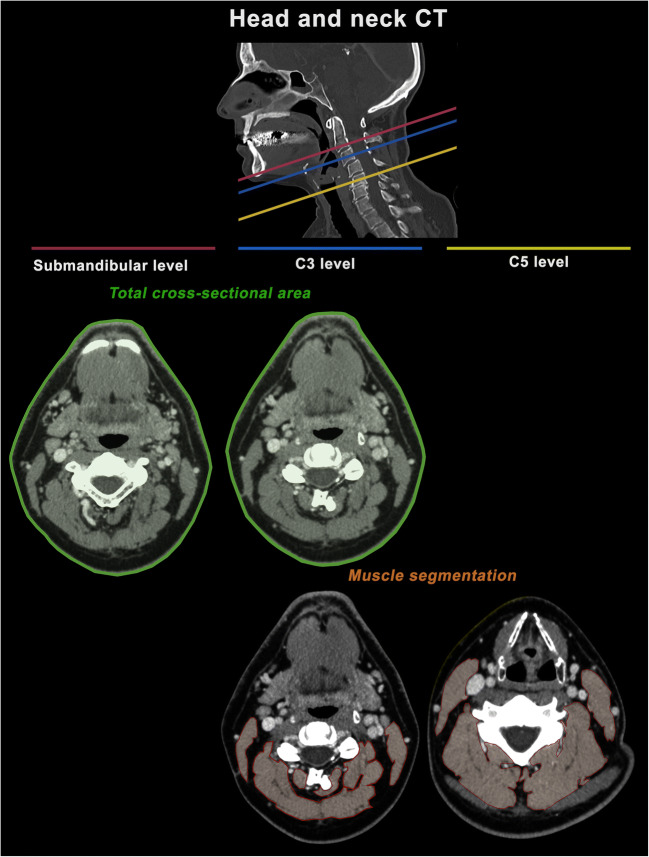

At the level of the neck, the total cross-sectional area of the patient’s body was measured at the height of C3 as well as submandibular. Furthermore, muscle areas of the sternocleidomastoid muscle and the autochthonous muscles were assessed at the height of the third and the fifth cervical vertebrae (C5). If the trapezius muscle was depicted at the level of C5, it was not considered. Analogously, the sum of all muscle areas was defined as the total cervical paraspinal muscle area at the height of C3 and C5, respectively. During ROI placement, small vessels or nerves within the muscles were included in measurements, as their contribution to the overall area appeared negligible. Figure 2 illustrates all cervical measurements.

Fig. 2.

Overview of the cervical 2D measurements to assess body composition. All measurements were performed using a freehand ROI tool within the standard PACS. The total cross-sectional area was measured at the submandibular level and at height of the third cervical vertebra (C3, outlined in green). Paraspinal muscle areas were measured at the height of C3 and at the height of the fifth cervical vertebra (C5, outlined in orange)